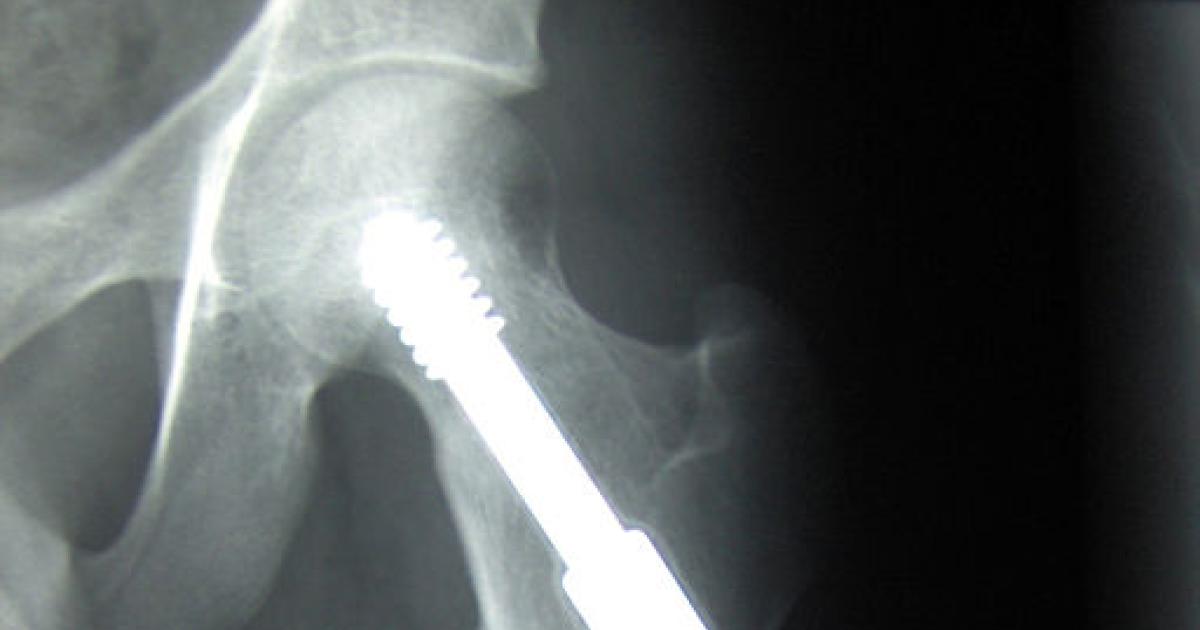

These fatigue induced fractures are frequently termed “stress fractures.” There is swelling of the bone’s surface and marrow, and subtle and tiny linear fractures; findings that normal X-rays studies are too insensitive to detect. The expense and radiation associated with MRI and CT imaging to screen for fractures are too great. More importantly, the patient’s complaints of increasing aches and pains in these bones that would prompt such studies are masked by other problems of aging, attributed to “arthritis” or getting old rather than formation of stress fractures. Measurement of collagen crosslinking, by those advanced glycation end products, is a future consideration.